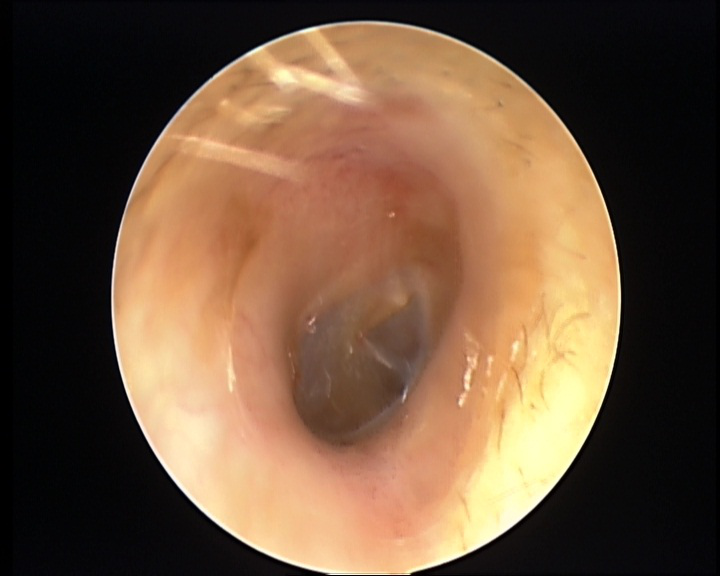

“医生 ,我的耳朵里面好痒 , 还感觉听不太清楚了,你快帮我看看吧!” 近日 , 30岁的小思神色紧张地来到海宁市一三甲医院耳鼻咽喉科就诊 。医生检查发现 , 他的 双侧耳道表面布满密密麻麻的白色绒毛物体 , 被诊断为“外耳道真菌病” 。△治疗前原来 , 前几天小思去当地采耳店享受了一次采耳服务 。“当时觉得很舒服 , 但几天之后就后悔了 , ”小思说 , 他 老感觉耳朵里很痒 , 而且像有一层纸堵住一样闷闷的。 “ 这两天在聊天时 , 也 总是听不清对方讲话 , 觉得听力都下降了 。”经过正规治疗后 , 小思的耳痒及耳闷症状逐渐好转 。△治疗后外耳道真菌病和采耳有关吗?